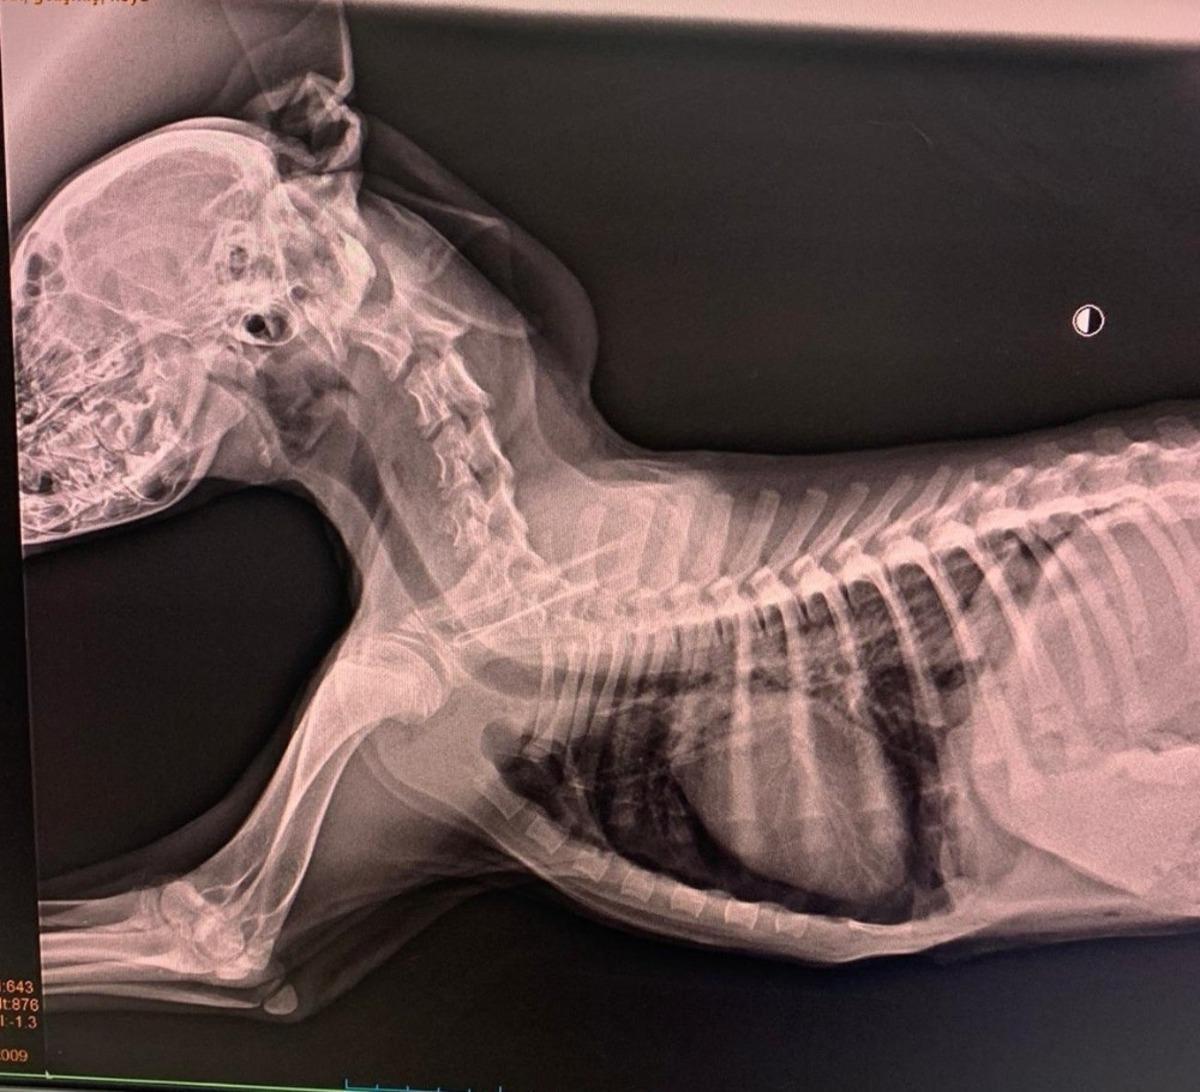

Sokak köpeği ameliyatla hayata döndürüldü